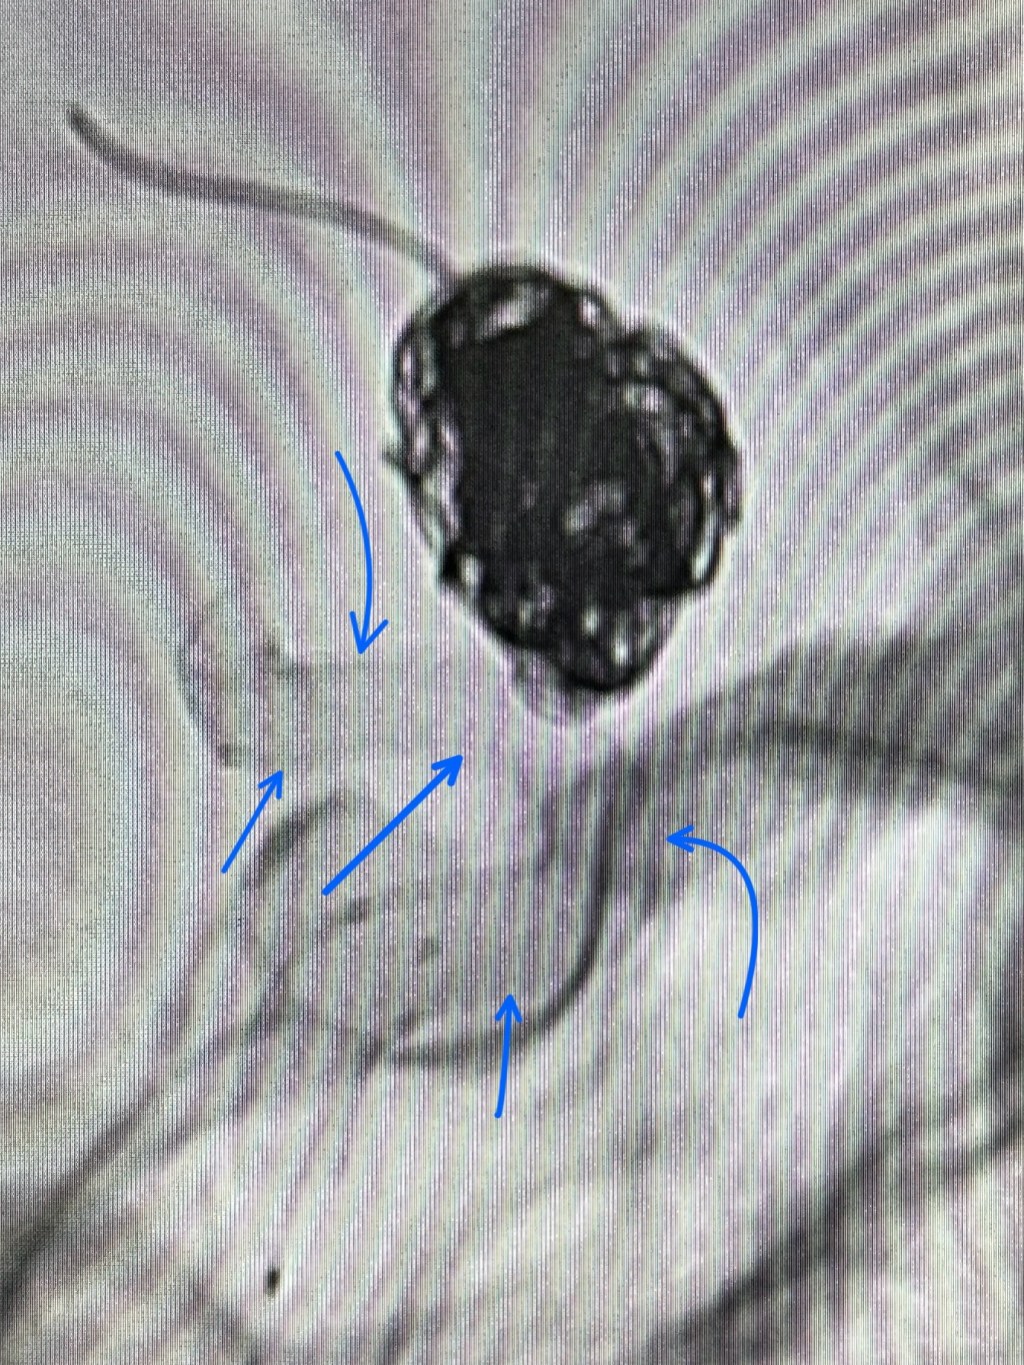

استخدمنا كمان دعامة كثيفة جداً، اسمها “الدعامة المغيّرة لمسار الدم” أو Flow Diverter. ودي دعامة مميزة جداً، فتحاتها صغيرة للغاية، وظيفتها إنها تغيّر اتجاه الدم وتمنع دخوله تماماً نحو التمدد، وده بيخلّي التمدد ينكمش مع الوقت ويقفل بشكل دائم. الدعامة دي معلّم عليها بالأسهم الزرقاء 🔵. هي مش دايماً بتكون واضحة في الصور، لكن لو ركزتوا هتشوفوها.